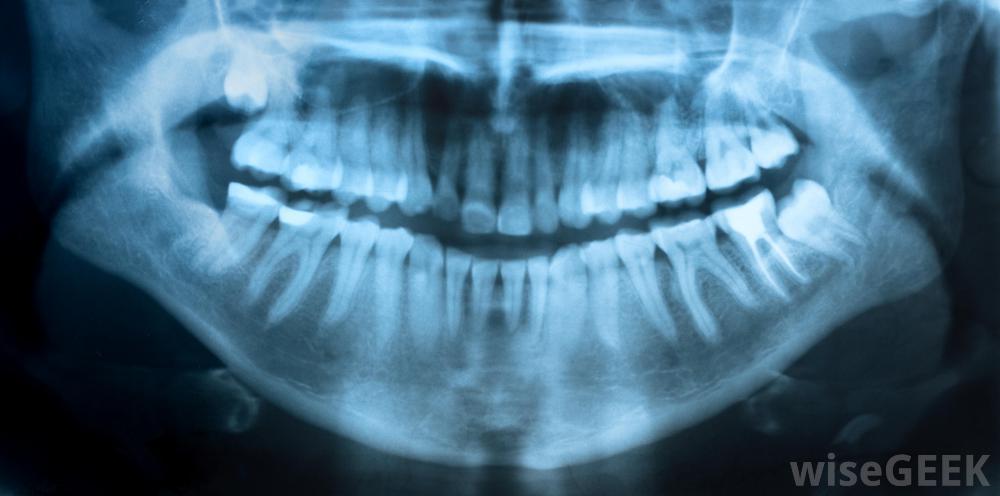

牙科醫生現在使用的x光片有很多種。牙科全景x光片是一個人整個口腔的全景圖,這使牙醫在一張照片中可以清楚地看到所有牙齒,這使他更好地了解牙齒在頜骨中的健康狀況和位置通常對患者進行牙科全景x光檢查;牙科全景x光片對于識別智齒的問題尤其重要。智齒是位于口腔后部的牙齒。標準的x光很難捕捉到整個牙齒因為智齒根區很深。牙科全景x光片可能有助于識別智齒的問題X光片提供了整個口腔區域的廣闊視野,這使牙醫能夠洞察到其他潛在的牙齒問題。這張照片包括了人類頭部的頜骨、頸部和鼻竇區域。這可以幫助牙醫確定頜骨區域的任何錯位,這可以影響一個人的咀嚼習慣。牙科全景x光片可以讓牙醫全面了解患者的牙齒全景x光片使用特殊膠片,不放在病人的嘴里。這與標準的咬翼x光片不同。全景x光片依靠先進的技術,可以穿透頭部和牙齒,類似于胸部x光片大多數牙醫在第一次就診時都會進行全景牙科x光檢查。這提供了牙齒的快速照片,以幫助牙醫確定潛在的齲齒。牙醫通常需要額外的單張照片來顯示全景圖中發現的特定牙齒問題牙科全景x光檢查需要幾分鐘才能完成。牙科醫生通常會要求患者坐著,而機械x光機在頭部周圍移動。這個過程無痛,但可能有點嚇人許多人擔心牙科醫生的x光機的輻射劑量。這種類型的x光片與標準的胸部x光片相比是適度的。x光片產生的輻射比一般的胸部x光片少三分之二。這個劑量相當于三張標準的牙齒照片牙科全景x光片不是每年都需要的。大多數牙醫要求每五年進行一次新的全景檢查,這樣就可以進行充分的檢查和覆蓋,以確定頜骨區域或智齒的潛在問題大多數牙科保險政策都會在不經常的時間間隔內進行牙科全景x光檢查。這種x光片比標準的咬翼x光片更貴,但由于它只需一張照片就可以覆蓋整個口腔,因此被認為更有效。在看牙醫之前,最好先查看一下具體的牙科保險單,以了解費用已覆蓋。無需每年進行牙科全景x光檢查。